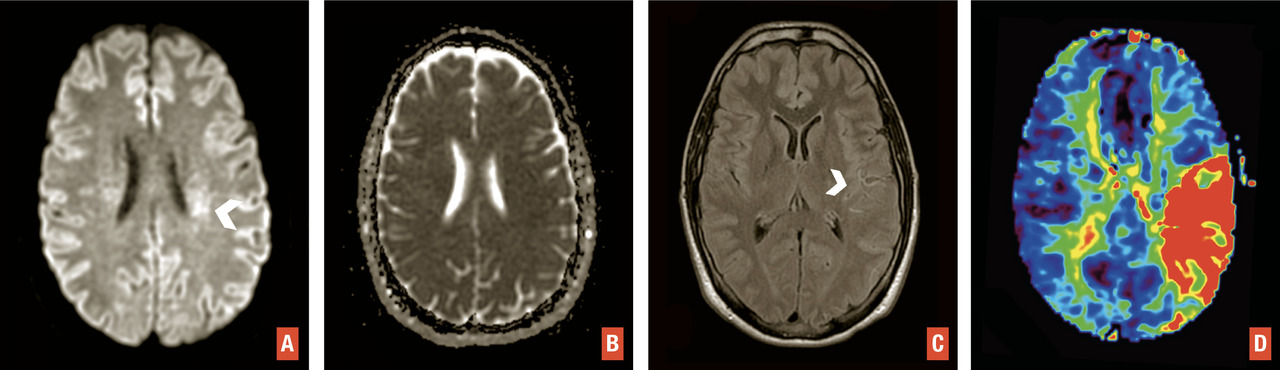

L’IRM est l’examen recommandé en France, si le plateau technique le permet sans retarder la prise en charge, et en dehors des contre-indications. Elle a une excellente sensibilité et spécificité pour détecter l’ischémie cérébrale aiguë. Un protocole standardisé est réalisable en moins de 10 minutes sans retarder la décision thérapeutique3 avec quatre séquences clés (– la séquence de diffusion pour détecter des lésions ischémiques récentes, en hypersignal avec baisse du coefficient apparent de diffusion, traduisant la restriction des mouvements des molécules d’eau secondaire à l’œdème cytotoxique. Bien que plus sensible que la tomodensitométrie, de rares faux négatifs peuvent s’observer en séquence diffusion en cas de lésion de petite taille, notamment de la fosse postérieure, d’examen très précoce ou de déficit transitoire ;

– la séquence de susceptibilité magnétique (T2* ou SWI) pour détecter un hématome,1 des séquelles hématiques ou une transformation hémorragique de lésions ischémiques, en particulier après traitement de recanalisation. Le thrombus artériel apparaît en hyposignal artériel linéaire ou curviligne en T2*, dont la sensibilité varie selon la composition du caillot, sa taille et le type de séquence utilisée ;

– la séquence FLAIR, qui permet d’apprécier l’étendue de la leucopathie vasculaire et les séquelles d’infarctus anciens, de dater l’infarctus (classiquement non visible avant 3 heures),1 de rechercher des hypersignaux vasculaires, en rapport avec des ralentissements vasculaires dans les artères collatérales en aval de l’occlusion ;

– l’angiographie par résonance magnétique (angio-IRM) 3D temps de vol du polygone de Willis (sans injection) afin de rechercher une occlusion ou une sténose des artères intracrâniennes. La séquence de perfusion T2* peut également être réalisée. Comme en tomodensitométrie, elle permet d’apprécier le risque d’extension de l’infarctus (« mismatch » perfusion-diffusion) et de décider d’un traitement de recanalisation dans des situations particulières (heure de début des symptômes inconnue, délai tardif)1 [